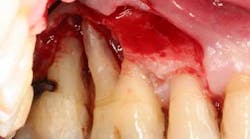

We saved three out of four molar areas (which have been functioning for 15 years now). The lost area is at teeth nos. 2 and 3. I remembered later that they had been damaged in an earlier dental matter. Tooth no. 2 was very loose, and no. 3 had a big crack in it.

After these teeth were removed, I tried getting a dental implant to replace no. 3, but for whatever reason, I was not comfortable, so we abandoned that treatment. I am now edentulous in that area, and I was advised to eat on the other side. Thus, our adventure began.